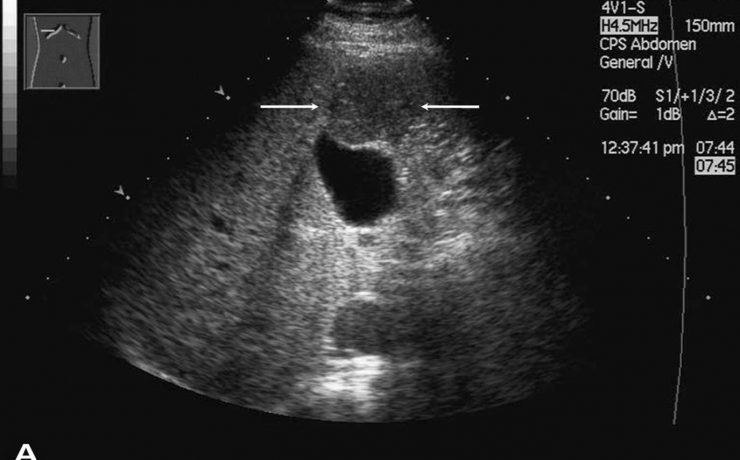

Patología fetal segundo trimestre

El RCIU constituye una de las mayores complicaciones del embarazo en. En incidencia de 3 a 10% en países desarrollados y 30% en países en vías de desarrollo. Recién nacidos con RCIU expuestos a riesgos de morbimortalidad neonatal por asfixia perinatal, encefalocele, hipoxia –isquémica, circulación fetal persistente, enterocolitis necrosante etc…